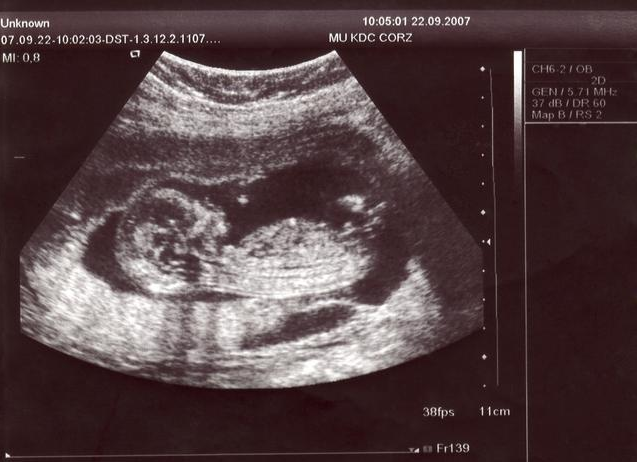

四維彩超是一種先進(jìn)的醫(yī)學(xué)成像技術(shù),能夠在孕期實(shí)時(shí)觀察胎兒的發(fā)育情況,與傳統(tǒng)的二維、三維彩超相比,四維彩超能夠提供更清晰、更立體的圖像,讓準(zhǔn)父母更直觀地了解胎兒的成長(zhǎng)過程。

胎兒的性別由性染色體決定,男性擁有一個(gè)X染色體和一個(gè)Y染色體,而女性則擁有兩個(gè)X染色體,在孕期,通過四維彩超可以觀察到胎兒的生殖器官,從而判斷胎兒的性別。

1、選擇合適的時(shí)間:在孕期20周以上進(jìn)行四維彩超檢查較為適宜,此時(shí)胎兒的生殖器官已發(fā)育到一定階段,圖像較為清晰。

2、觀察圖像:在四維彩超圖像上,男性胎兒的生殖器官呈現(xiàn)為細(xì)小的小雞冠狀結(jié)構(gòu),而女性胎兒的生殖器官則呈現(xiàn)為較為平滑的橢圓形結(jié)構(gòu),通過觀察這些特征,可以初步判斷胎兒的性別。

3、識(shí)別誤區(qū):在觀察四維彩超圖像時(shí),需要注意避免受到其他身體部位(如臍帶、胎盤等)的干擾,胎兒的體位也會(huì)影響觀察結(jié)果,因此可能需要多次檢查才能確定。

(此處可插入一系列四維彩超圖像,展示男性胎兒和女性胎兒生殖器官的不同特征)